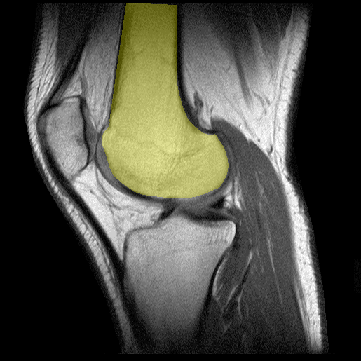

El fémur distal muestra los cóndilos lateral y medial

para su articulación con la tibia. El cóndilo medial se

extiende más distalmente que el cóndilo lateral. Los cóndilos

están separados por una depresión llama "fosa intercondílea".

Próximos a los cóndilos se sitúan las tuberosidades

interna y externa del fémur donde se insertan los ligamentos

lateral interno y lateral externo, respectivamente. En la fosa intercondílea

se insertan los ligamentos cruzado anterior y cruzado posterior. |